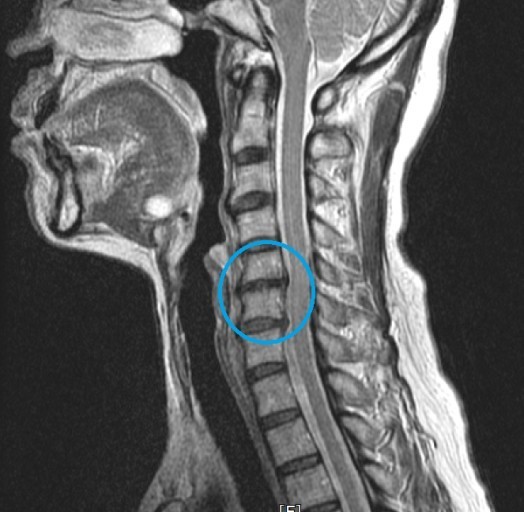

목디스크 증상 목디스크란 목 뼈 사이의 디스크가 원래의 자리에서 이탈하면서 신경을 누르거나 뼈조직이 비정상적으로 자라나 목을 지나가는 척추신경을 누르게 됨으로써 통증을 느끼는 질환입니다. 예전에는 40대 이상의 분들한테서 주로 나타나는 질환이었지만 요즘은 젊은 세대에도 흔하게 볼 수 있는 질환이 되었습니다.

목에 통증이 발생되는 것은 목디스크 증상 중에서 매우 처음 발생하는 증상이죠. 목이 계속 뻐근한 느낌이 들뿐만 아니라 고개를 살짝만 돌리더라도 통증이 느껴질 때가 있으며 심한 해당에는 아예 머리를 돌리지 못하게 돼요.

목디스크가 심한 해당에는 어깨뿐만 아니라 팔과 손가락에도 저림을 동반한 고통을 느끼실 수 있다. 디스크의 수핵이 빠져나가거나 퇴행성 경추 척추증 및 경추관 협착증 등으로 척수가 눌리게 되면 대개는 팔의 힘이 빠지는 느낌을 받을 수 있다. 이러한 해당에는 팔을 머리 위로 들면 고통이 완화되는 해당이가 있는데 일시적일 뿐 목디스크의 전형적인 증상이니 꼭 정형외과에 방문하셔서 전문의에게 상담을 받아보시길 권장드린다.